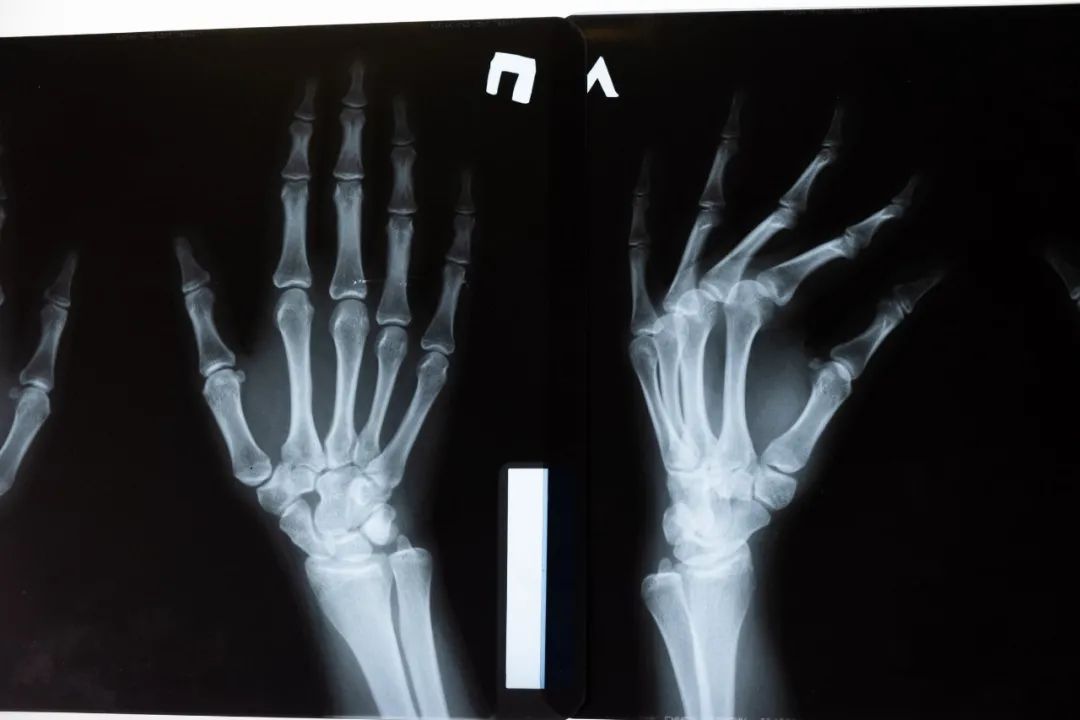

骨质疏松者是不可以接受正骨治疗,手法的力度控制不好也很容易出现骨折等医疗事故。

诊断不明,不知其治疗要领的疾病(比如骨折、骨裂和颈椎脱位等),也应视为禁忌症。